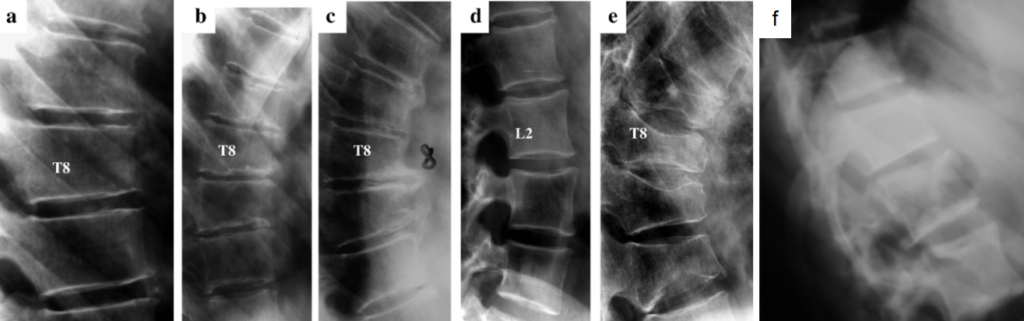

Uno degli aspetti più complessi della morfometria è la diagnosi differenziale. Non tutte le vertebre che presentano una riduzione dell’altezza sono fratture da fragilità. Una corretta interpretazione richiede la distinzione tra “frattura” e “deformità non fratturativa“.10

Oltre allo Scheuermann, il clinico deve prestare attenzione a:

- vertebra a farfalla: una malformazione congenita in cui il corpo vertebrale appare diviso in due ali, simulando un crollo severo;

- short vertebral height: condizione di statura vertebrale costituzionalmente bassa ma con limitanti regolari e prive di segni di fragilità;

- spondiloartrite e osteofiti: i processi degenerativi possono produrre escrescenze ossee (osteofiti) che vengono interpretate erroneamente dal software come parte della vertebra, alterando i calcoli delle altezze;12

- localizzazioni neoplastiche: le fratture patologiche dovute a metastasi ossee o mieloma multiplo possono simulare i crolli osteoporotici. Segni di allarme sono l’interessamento del muro posteriore, la presenza di masse nei tessuti molli o una riduzione asimmetrica dell’altezza posteriore superiore a quella anteriore.

(a) varianti anatomiche, come la fisiologica cuneizzazione delle vertebre dorsali

(b) esiti di osteocondrosi giovanile, come la Malattia di Scheuermann

(c) deformazioni conseguenti a processi degenerativi di natura artrosica

(d) ulteriori varianti anatomiche, come le vertebre lombari a cuneo invertito

(e) fratture da fragilità su base osteoporotica

(f) esiti di pregresse fratture di origine traumatica